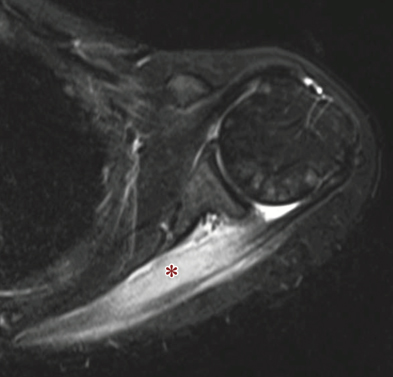

- 【脊椎関節炎(SpA)での肩関節病変】

腱板炎、大結節(腱付着部)のエロージョン、付着部の骨髄浮腫が特異的所見である。

関節包周囲軟部組織の浮腫および造影効果は関節リウマチより高度である。

反応性関節炎は下肢優位の病変分布とされているが、肩関節病変をきたすこともある。